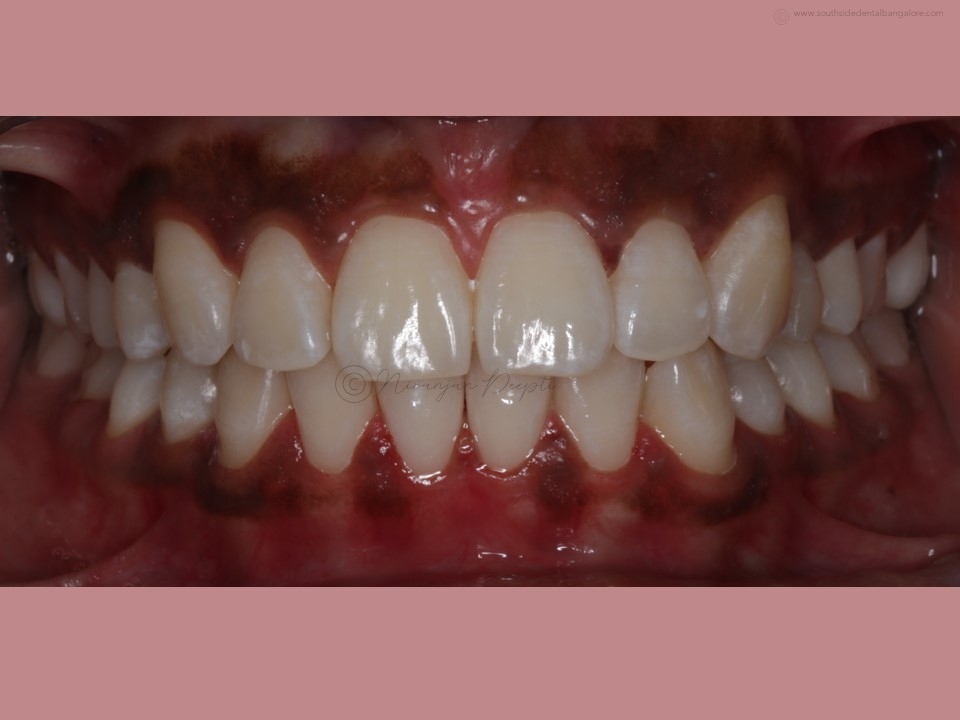

Polishing of teeth after the debonding of braces is a crucial step in the orthodontic treatment process.

- Enhances Aesthetics: Polishing creates a polished, uniform appearance, enhancing the overall aesthetics of your smile and boosting your confidence post-braces.

- Polishing: Using a specialized dental tool, your orthodontist/dentist will carefully polish each tooth surface to remove any remaining adhesive residue and smooth out imperfections.

- Fluoride Treatment: Following polishing, a fluoride treatment may be applied to strengthen the enamel and protect against decay.

- Final Evaluation: Your orthodontist/dentist will evaluate the results to ensure that the teeth are properly polished and free from any residual materials.

By following these guidelines and maintaining good oral hygiene practices, you can enjoy a beautiful, healthy smile for years to come after the debonding of braces.